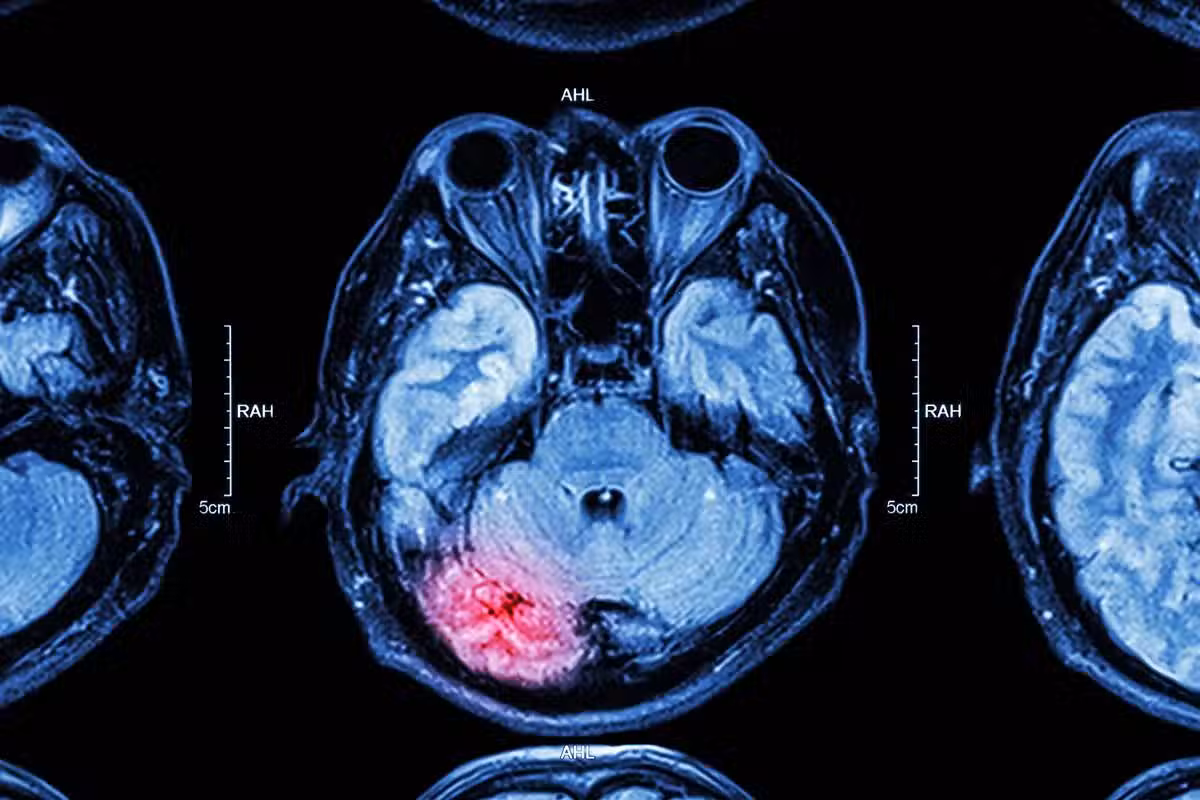

通常情況下,當血管內壁的斑塊積聚時,會引發動脈粥樣硬化這一病癥。這些斑塊會逐漸硬化並使血管的直徑減小,從而限制了血液對組織和器官的供應。身體內的任何動脈都可能出現斑塊,包括大腦和頸部的動脈。這些斑塊在大腦和頸部形成,是缺血性中風的常見原因之一。

另外斑塊破裂時,血小板會迅速在斑塊受損部位集結,形成血栓,這些血栓同樣會引發動脈的阻塞。而一旦血栓脫落,它們將有可能游移至大腦阻塞腦動脈,形成缺血性中風。某些心臟、血液疾病,如心房顫動和鐮狀細胞病,就會導致血栓形成,進而可能引發缺血性中風。